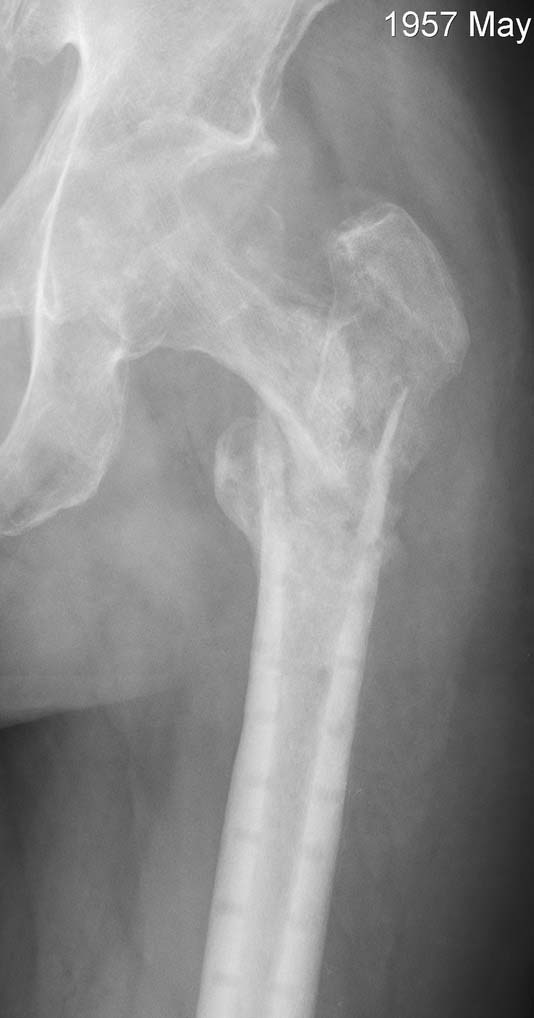

Пациент 55 лет, оперирован клинковой 130 градусной пластиной 6 месяцев назад. После удаления пластины - клинически и рентгенологически несращение.

Хороший пример того, что если сразу не все в порядке, то надеятся на чудо не следует. Пациент 55 лет, оперирован клинковой 130 градусной пластиной 6 месяцев назад (не в нашем ауле:). В надежде на сращение перелома выжидали до 6 месяцев после операции. По предварительным снимкам и КТ было ощущение какой-то консолидации. После удаления пластины - клинически и рентгенологически несращение. На КТ - дефект головки (как и следовало ожидать). Явных признаков инфекции нет. На операции незначительное количество прозрачной "синовиальной" жидкости (взят посев, результат будет через день-два). Не температурит. СОЭ перед операцией 17.

На сегодня беспокоят боли в области несращения, нога не опорна. Рана после удаления фиксатора заживает спокойно (7 дней после операции).

Рентген до, полсе и КТ на сегодняшний день в приложении.